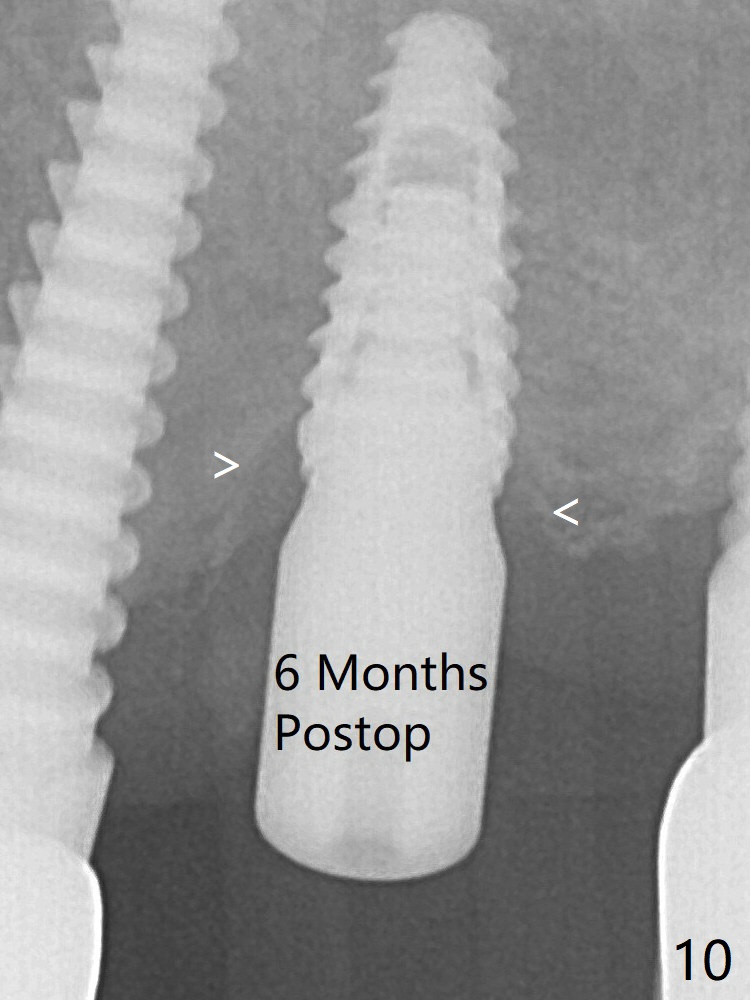

A 4x6 mm healing abutment is inserted (Fig.3).  There is crestal bone loss 6 months postop (Fig.10 arrowheads).